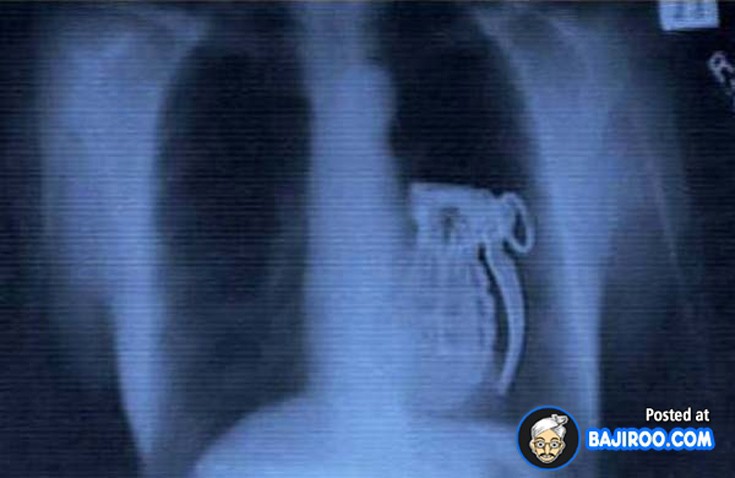

Ο,ΤΙ ΝΑ 'ΝΑΙ #ακτινογραφίες Παράξενα πράγματα που έχουν δείξει οι ακτινογραφίες Από δαχτυλίδια μέχρι πιρούνια και καρφιά - Δείτε τις φωτογραφίες 15·04·2016 11:08 1 σχόλια